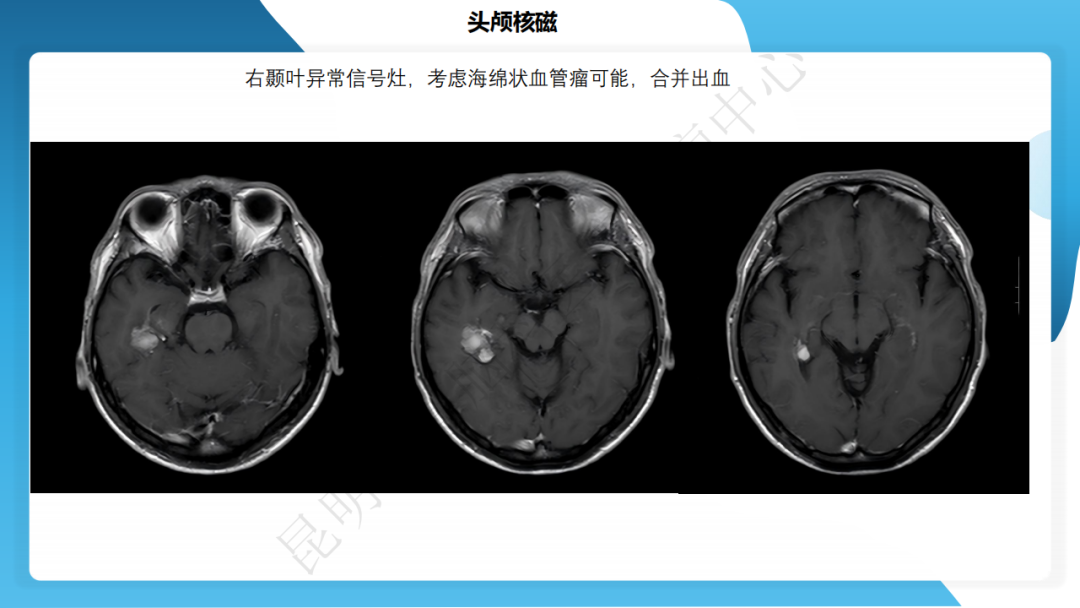

攻克难治性癫痫!右颞开颅术成功切除海绵状血管瘤,患者重归正常生活